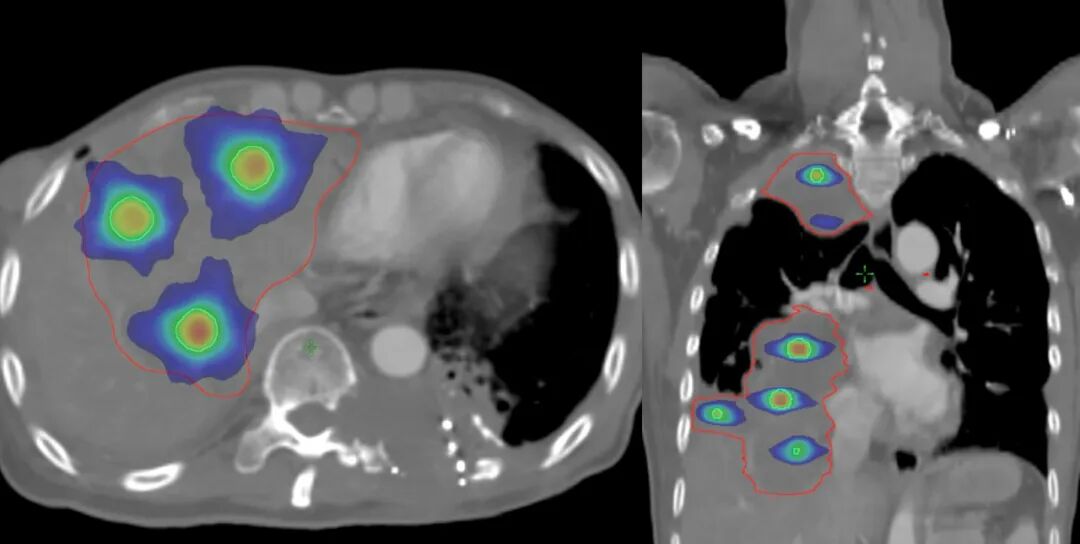

鑒于患者腫瘤體積龐大且臨近多個重要器官,放療團隊經(jīng)深入討論,決定為患者實施空間分割放射治療。潘振宇教授制定了照射方案:前3次每次15Gy,高劑量集中照射腫瘤內(nèi)部小部分體積,其余部分腫瘤體積進行常規(guī)劑量照射,治療方式為隔天照射;后15次每次3Gy,照射全部腫瘤體積,每周5次。孫行儒物理技術(shù)組長進行了放射治療方案設(shè)計,以及放射治療計劃劑量驗證,保障了放療計劃的精準(zhǔn)投照。

圖注:放射治療靶區(qū)及劑量分布圖。紅線是放射治療靶區(qū);綠色球體為放射治療高劑量分布,可見聚焦照射,周邊劑量快速跌落,周圍組織受到良好保護。